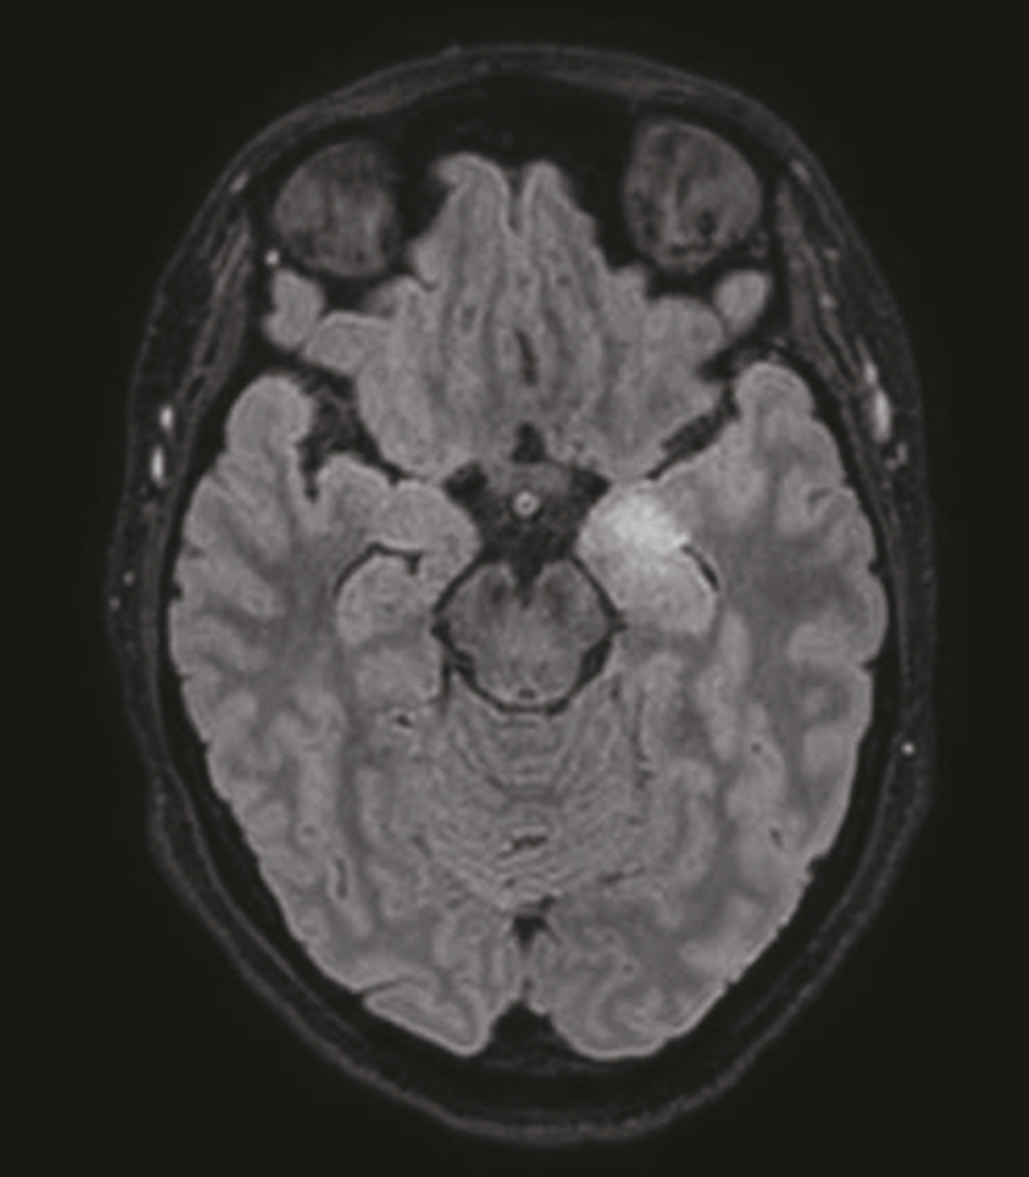

L’imagerie par résonance magnétique (IRM) cérébrale peut montrer un hypersignal T2 temporal interne unilatéral ou bilatéral ne prenant pas le contraste (fig. 1 ), mais peut également être normale.2, 3 L’électroencéphalogramme (EEG) peut mettre en évidence une focalisation aux régions temporales (ralentissement, activité paroxystique).2 L’étude du liquide cérébrospinal (LCS) peut trouver des signes d’inflammation (pléiocytose, bandes oligoclonales) ou être normale.3

L’IRM cérébrale visualise un hypersignal temporal interne dans seulement un tiers des cas (fig. 1 ). L’EEG peut révéler des signes évocateurs, comme l’extreme delta brush*, notamment dans les formes sévères, mais le plus souvent le tracé est simplement ralenti et désorganisé.2